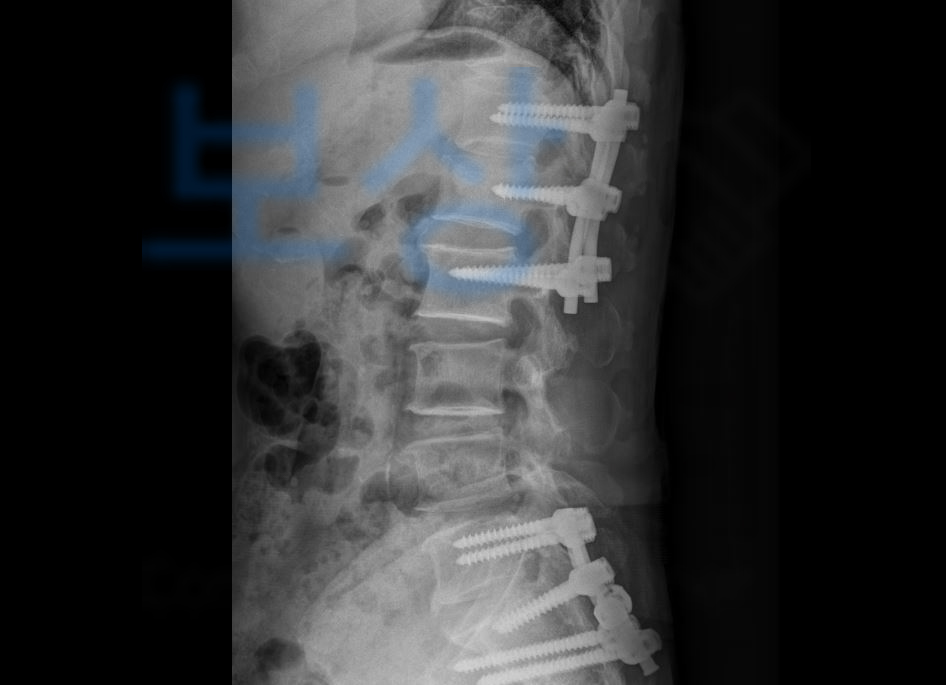

진단을 받으셨고 골절의 모양이 좋지 않아 척추 후방고절술 즉 후방유합술을 받아 안정을 취하셔야 했습니다.

보상파트너는 이@@님의 영상CD를 함께 보며 보상의 범위가 어느정도 가능할지 기본적인 상담을 도와드렸고 상주하는 노무직원과 함께 장해급여 신청부터 지급까지 함께 진행하게 되었습니다

산재 장해등급 10급

산재 보상금 일시금 총 27,120,320원 받게 되셨습니다!